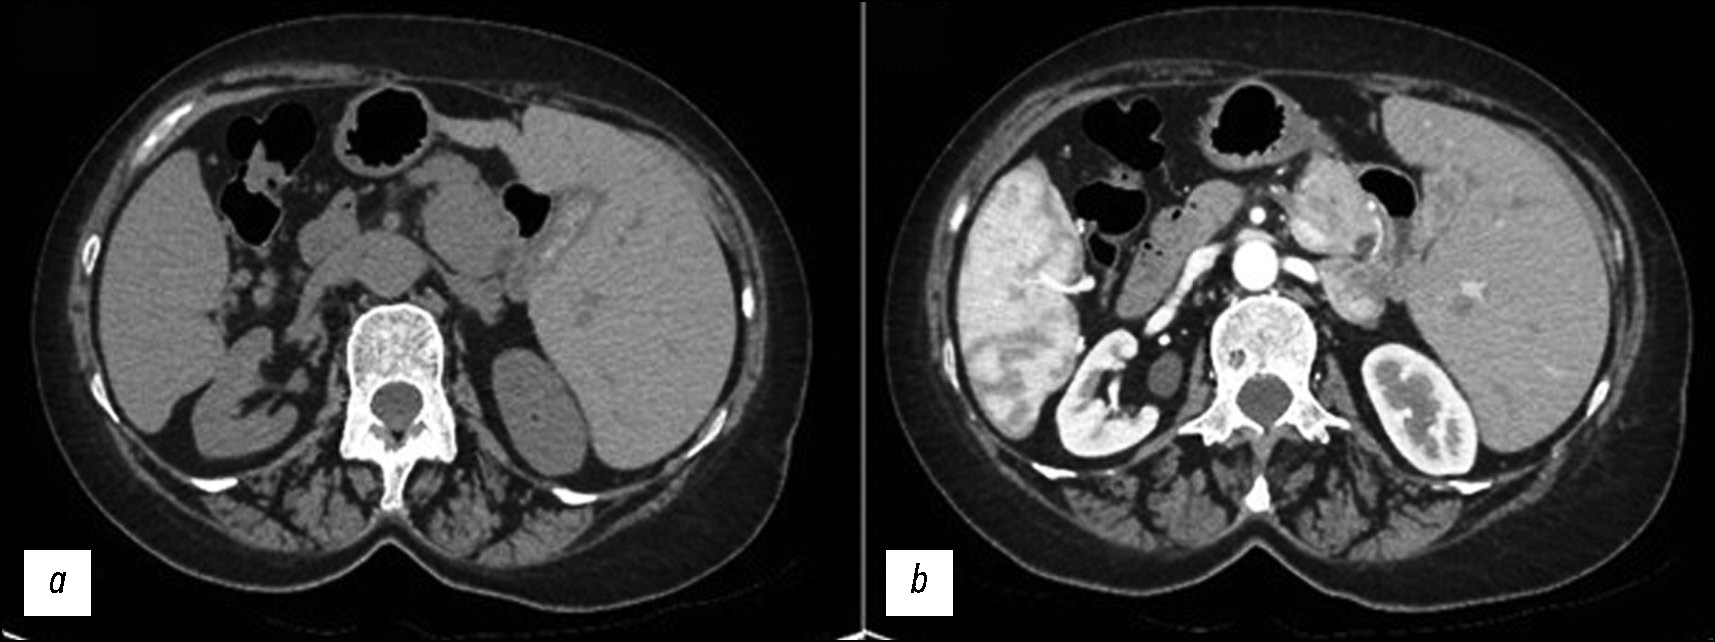

This case is not directly related to significant symptoms or acute problems due to SIT; instead, the interventions were focused on critical symptoms and the management and prevention of complications [12–16]. Biliary colic treatment aims to reduce pain with painkillers and antispasmodics to relieve symptoms (Fig. 5).

Fig. 5. The gallbladder appears with multiple calcific calculi. These CT images without (a) and with (b) contrast medium justify the left-sided abdominal pain.